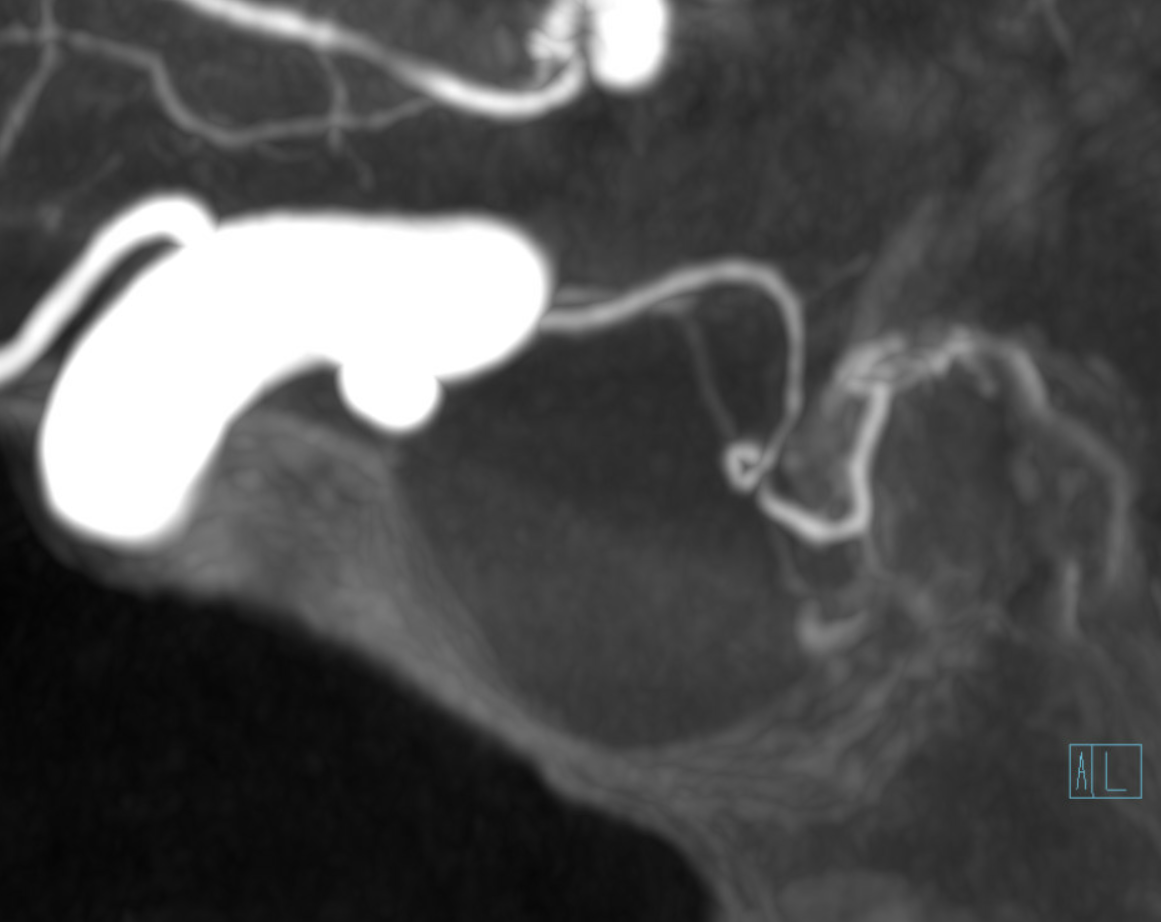

MIP image shows the sella nicely — and helps prove its posterior pituitary

Of course, there is an aneurysm here — the branch point camp would point out how this larger than usual branch is a setup for aneurysmal formation. Naturally…